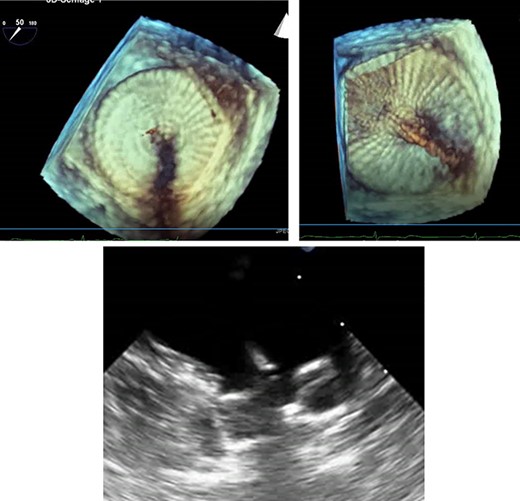

An LAA clip was implanted, under general anaesthesia with a double lumen tube, via a left mini-thoracotomy without a heart-lung machine. Briefly, a 7 cm skin incision was made laterally above the left mamilla (Fig. 4). Preparation of the subcutis and pectoralis muscle in the fourth intercostal space exposed the LAA. The LAA clip (AtriCure 40 mm) was placed over the LAA to its base. Transoesophageal echocardiography was used to complete LAA closure, the clip was closed and holding device removed (Fig. 5). The patient received 2.5 mg fondaparinux once daily to prevent thrombosis formation; once mobile anticoagulation was stopped. Five days post intervention, the patient was discharged in good clinical condition. Wound healing was uneventful at 10 days. After 1 year without anticoagulation, no further complications were observed.

Transoesophageal echocardiography control of the LAA clip in correct position at the LAA base with display of the complete LAA closure.